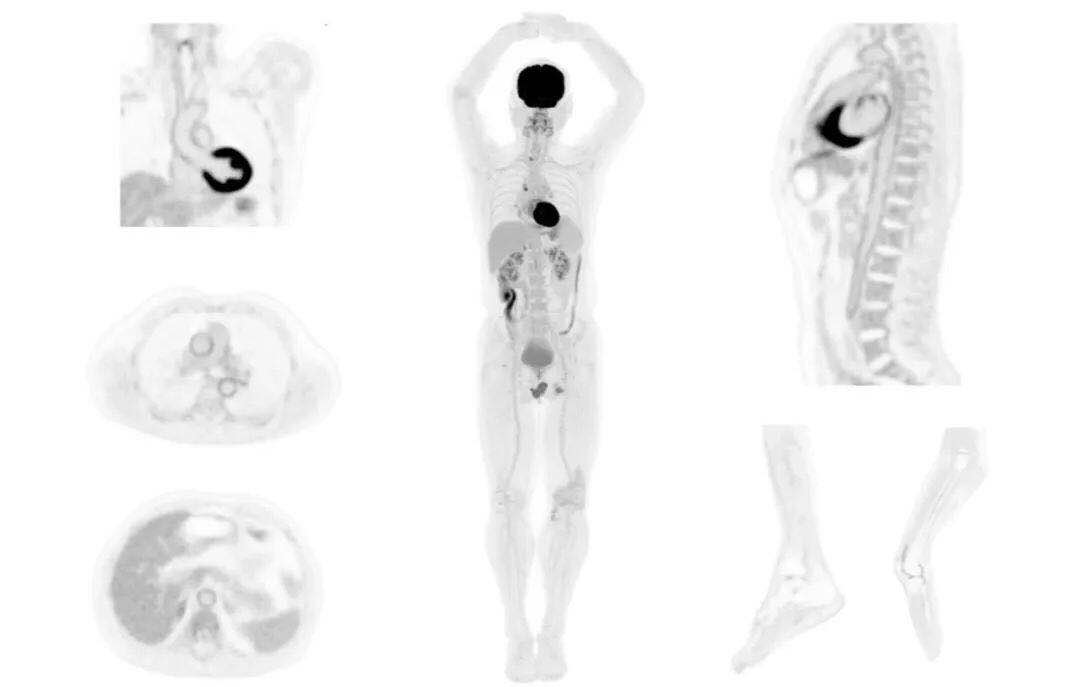

圖例

uExplorer探索者不再局限于傳統(tǒng)靜態(tài)代謝過程3D成像,而是在此基礎(chǔ)上新增一個維度——時間,從而實現(xiàn)4D全景成像。

注射總劑量為7.8mCi,14分鐘全身采集時間,在擁有超高靈敏度與超高分辨率的uEXPLORER上,即可得到展示顯示人體諸多精細(xì)結(jié)構(gòu)的高清三維圖像。

注射總劑量為7.8mCi,注射后1.6小時,基于uEXPLORER探索者掃描1分鐘的圖像

注射總劑量為0.67 mCi FDG(低于常規(guī)劑量的十分之一),基于uEXPLORER探索者掃描15分鐘的圖像

注射總劑量為6.9mCi,注射后10小時,基于uEXPLORER探索者掃描14分鐘的圖像